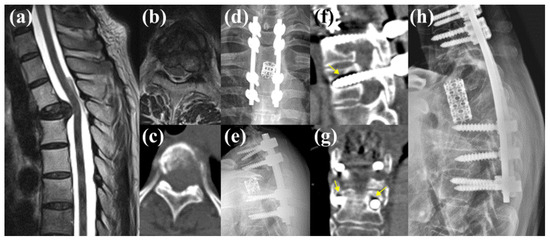

3.5.1. Case 1